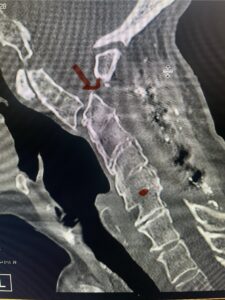

Cervical x-rays revealed a significantly increased atlanto-axial interval (Fig. 5) On review of her imaging studies it was noted that the right C2 isthmus was very thinned by the vertebral foramen (Figs 6a, b, and c) which would make an attempt at placing a C2 pars screw dangerous. A decision was made to perform an occipital-cervical fusion because only possible unilateral fixation and an extensive C1 laminectomy to be performed eliminating a fixation point if a more traditional C1-C2 was performed. Even if C1 lateral mass screws were able to be placed one could only perform a unilateral screw construct fixation to C2. We performed an occipital cervical fusion down to C4 to get enough inferior fixation and C1 laminectomy. The decompression went well. We placed a left unilateral pars screw and bilateral C3 and C4 lateral mass screws. We placed three 12 mm screws in the midline keel (Fig. 7). Postoperatively the patient had all around improvement in her symptoms and did not qualify for rehab. Her post op films at 6 weeks (Fig. 8)

Fig. 6a: Sagittal cervical CT scan demonstrating an abnormally thin right C2 isthmus prohibiting safe placement of screw (red arrow). Notice the vertebral foramen eroding the isthmus bone structure (red dot).